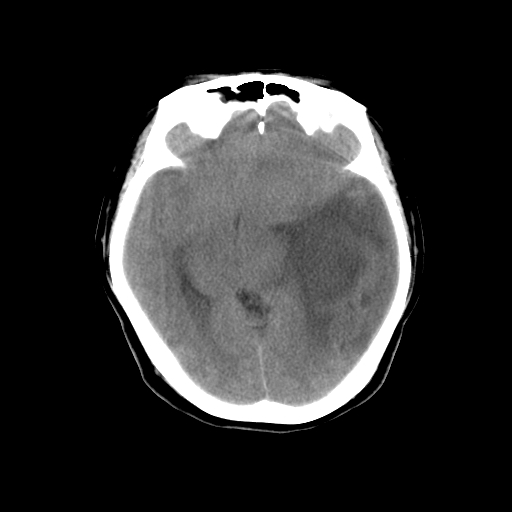

标题: CT14513:女性41岁,头部不适二月余,其它病史不详。请分析 [打印本页]

标题: CT14513:女性41岁,头部不适二月余,其它病史不详。请分析

1.考虑:左侧颞顶叶星形细胞瘤。2.大脑镰下疝。

支持!但楼主所提示处颅骨明显受压变薄,是否有合并蛛网膜囊肿或局部硬膜下水瘤的可能?脑穿通畸形暂不予以考虑:明显占位表现;病侧脑室无扩张;病灶不是较明确的脑脊液密度;边界不清晰。还是mri检查吧,提供的有价值信息更多一些,至少可以排除或肯定蛛网膜囊肿或局部硬膜下水瘤的存在。

1)考虑左侧颞顶叶胶质瘤。2)左侧颞顶部慢性硬膜下血肿?3)大脑镰下疝。